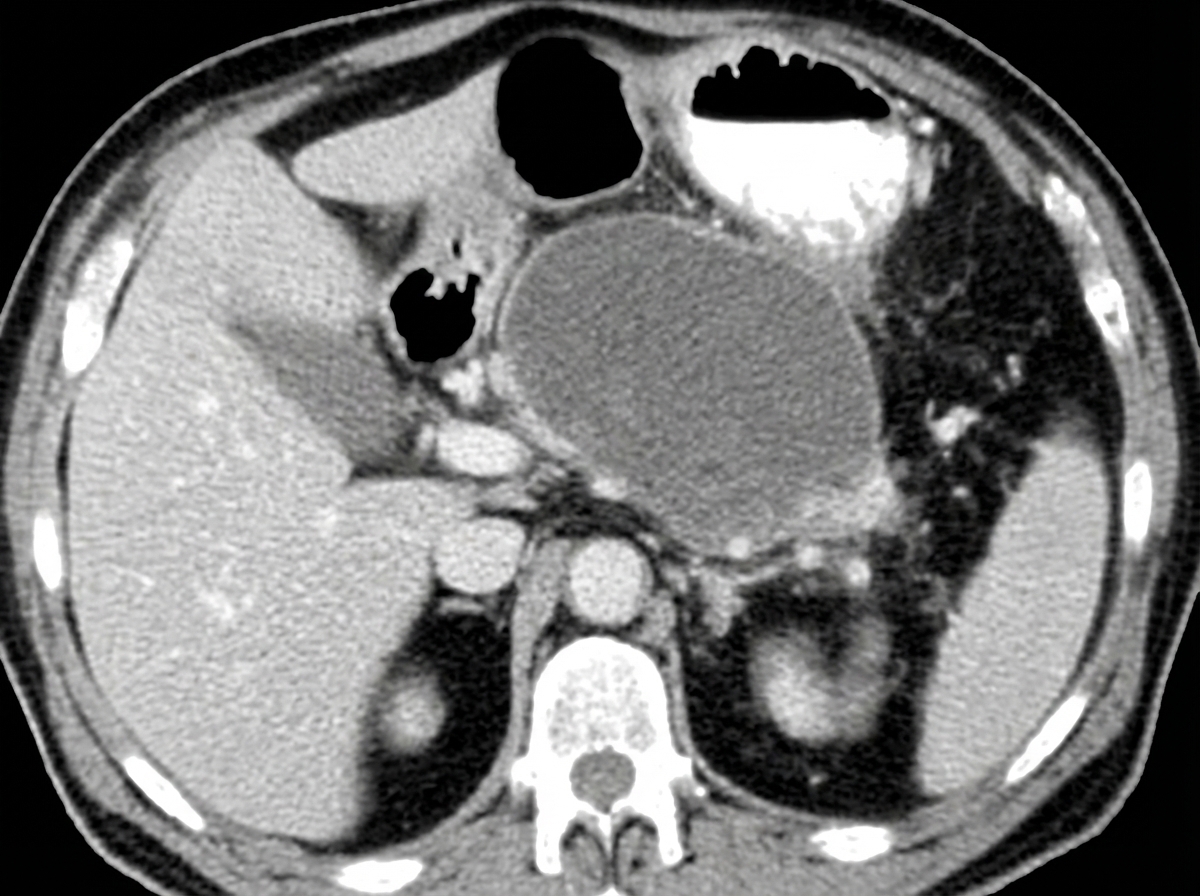

Explanation: ***Pseudocyst*** - **CECT** shows a **fluid-density collection** with **thin walls** in the peripancreatic region, which is characteristic of a **pancreatic pseudocyst**. - The **non-bilious vomiting** occurs due to **gastric compression** by the pseudocyst, commonly seen in chronic alcoholics with recurrent pancreatitis. *Gastric outlet obstruction* - Would show **gastric distension** and **delayed gastric emptying** on CECT, but lacks the characteristic **peripancreatic fluid collection**. - Typically presents with **bilious vomiting** and **succussion splash**, which are not described here. *Carcinoma pancreas* - **CECT** would reveal a **solid mass** with **irregular margins** and possible **vascular encasement**, not a fluid collection. - Usually presents with **painless jaundice**, **weight loss**, and **abdominal pain**, rather than isolated post-prandial vomiting. *Chronic pancreatitis* - **CECT** shows **pancreatic calcifications**, **ductal dilatation**, and **parenchymal atrophy**, not a fluid collection. - Typically presents with **steatorrhea**, **diabetes mellitus**, and **chronic abdominal pain**, rather than episodic vomiting.